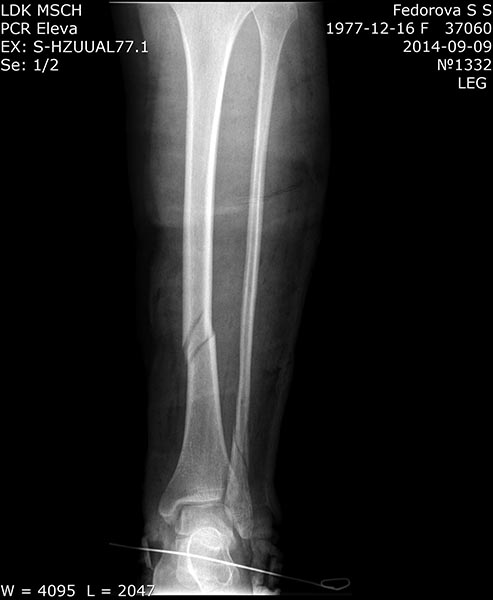

Добрвый день. Пациентка 37 лет, соматически здорова.04.09.14г.

Подвернула левую ногу, получила винтообразный перелом обеих костей н/з

левой голени со смещением отломков. В ЦРБ наложено скелетное вытяжение

за пяточную кость. При рентгенографии на вытяжении смещение отломков

большеберцовой кости устранено. Доставлена к нам на 4-е сутки в задней

гипсовой лонгете. Вот снимки при поступленни к нам в гипсе. Ваши

предложения по тактике лечения данного перелома?